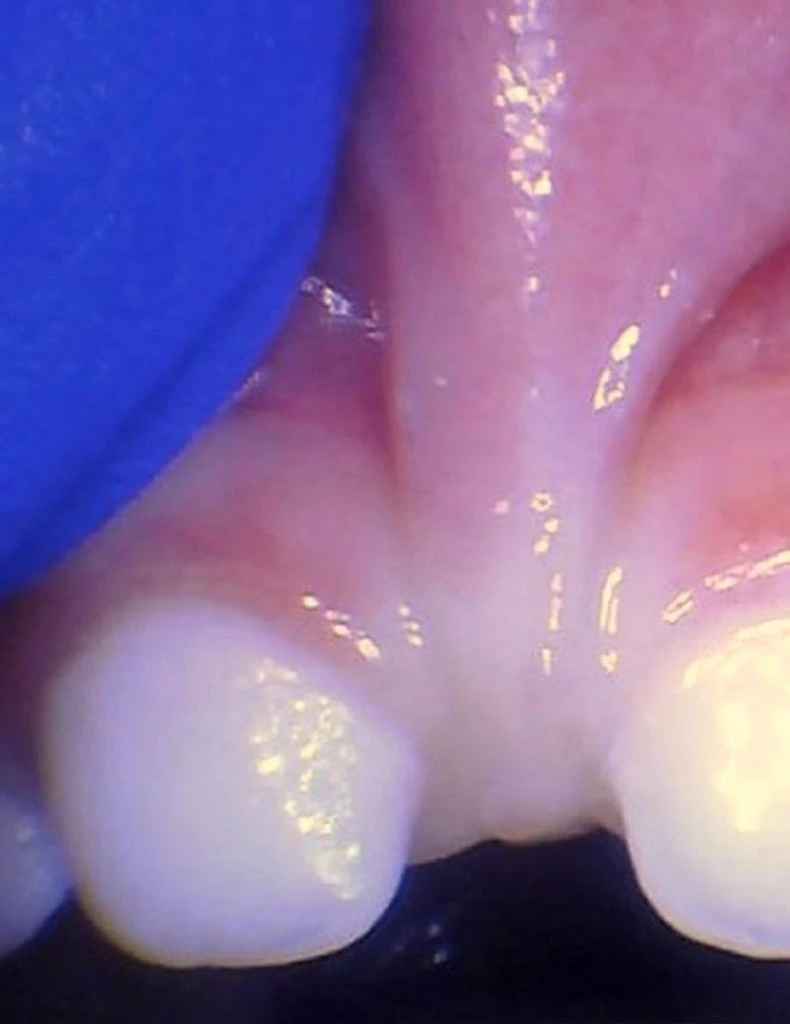

These images show the spectrum of lip restriction in an infant.

View lip restrictions

These images show the spectrum of lip restriction in a child.